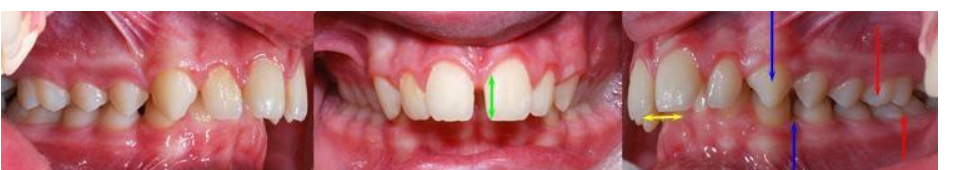

MFD EXAMS /23 6 1234567891011121314151617181920212223 You have 30 min to complete this exam. The timer will start once you begin Attention: Only a few minutes left! Please submit your answers soon. MFD 1 Get a quick sneak peek before the real exam !This trial quiz is designed to show you the question style, difficulty level, and how the options will appear on the platform. 1 / 23 1. What is the lethal dose and toxic dose of fluoride, management? Check 2 / 23 2. What the advantage of silver diamine over other methods and disadvantages ? Check 3 / 23 3. Method of topical fluoride application with concentration ? Check 4 / 23 4. What will happen if left untreated? Check 5 / 23 5. What changes that will happen if the habit stopped? Check 6 / 23 6. Give 3 of your initial stage of treatment? Check 7 / 23 7. What are the causes? Check 8 / 23 8. What is this? Check 9 / 23 9. Then they specified the type of pain and asked about the diagnosis Check 10 / 23 10. What other tests to check vitality of the pulp? Check 11 / 23 11. What are the factors will govern the Rx of Posterior cross bite ? Check 12 / 23 12. What are the factors that govern the treatment of anterior cross bite? Check 13 / 23 13. Name the appliance that you can use to treat this case? Check 14 / 23 14. Name 3 causes? Check 15 / 23 15. Name the most important clinical diagnostic information you need to know. (check RCSI intensive course )? Check 16 / 23 16. What do you see? Check 17 / 23 17. What is your treatment? Check 18 / 23 18. Name the investigations needed? Check 19 / 23 19. causes for gingival enlargement ? Check 20 / 23 20. What is the common side effect of this drug? Check 21 / 23 21. Name the drug that he may take to treat this condition? Check 22 / 23 22. The patient may have what? Check 23 / 23 23. What is this clinical condition? Check /31 2 12345678910111213141516171819202122232425262728293031 You have 30 min to complete this exam. The timer will start once you begin Attention: Only a few minutes left! Please submit your answers soon. MFD 2 Get a quick sneak peek before the real exam !This trial quiz is designed to show you the question style, difficulty level, and how the options will appear on the platform. 1 / 31 1. Mention 2 fixed space maintainers and 2 removable space maintainers other from mentioned : Check 2 / 31 2. Other space maintenance used for child lost primary second molar E before the eruption of the permanent molars ? Check 3 / 31 3. What are the difference between nance appliance and Transpalatal arch Check 4 / 31 4. What material used to attach band? Check 5 / 31 5. What instruction you give to patient? Check 6 / 31 6. Name other fixed space maintainer used in upper jaw and mechanism of their action? Check 7 / 31 7. What component of this appliance? Check 8 / 31 8. What is this appliance , for what its used ? Check 9 / 31 9. Treatment? Check 10 / 31 10. Define Abrasion and Erosion? Check 11 / 31 11. What does this picture show? Check 12 / 31 12. what investigations you can do ? Check 13 / 31 13. Drugs can lead to lichenoid reaction Check 14 / 31 14. What extra oral features in “ Lichenoid reaction )? Check 15 / 31 15. What microscopical features of it ( licheonoid reaction )? Check 16 / 31 16. Definitive diagnosis ? Check 17 / 31 17. Mention type of suggested biopsy ? Check 18 / 31 18. Mention 4 differential diagnosis ? Check 19 / 31 19. Mention 4 questions you will ask the patient ? Check 20 / 31 20. Give 4 intraoral decription of what you see ? Check 21 / 31 21. What the other surgery can be performed to make prothesis? Check 22 / 31 22. Can this tooth stand with fixed prothesis? (in the opg )à taken from Malek file ? Check 23 / 31 23. Radiograph of missing multiple teeth consider it according to Antes law? ON which tooth you will make Abutment ? Check 24 / 31 24. What is Antes law? Check 25 / 31 25. What is best one to use as abutment in fixed prosthesis A or B? Check 26 / 31 26. What relevance of this picture? Check 27 / 31 27. What’s complication of doing surgery in this area floor of mouth? Check 28 / 31 28. Other 2 radiograph needed in diagnosis? Check 29 / 31 29. Give 4 differential diagnosis? Check 30 / 31 30. What can you see ? Check 31 / 31 31. What is the name of radiograph? Check Your score is /30 1 123456789101112131415161718192021222324252627282930 You have 30 min to complete this exam. The timer will start once you begin Attention: Only a few minutes left! Please submit your answers soon. MFD 3 Get a quick sneak peek before the real exam !This trial quiz is designed to show you the question style, difficulty level, and how the options will appear on the platform. 1 / 30 1. Treatment? Check 2 / 30 2. Histopathology? Check 3 / 30 3. Differential diagnosis Check 4 / 30 4. Clinical features’? Check 5 / 30 5. Patient said, this lesion is very frequent, why? Check 6 / 30 6. What are the causes for ulcers? Check 7 / 30 7. Patient have other signs like uveitis ,Genital ulcerations which syndrome he had ? Check 8 / 30 8. Name of the lesion ? Check 9 / 30 9. Mention some TMJ movement ? Check 10 / 30 10. Blood supply ? Check 11 / 30 11. Nerve supply ? Check 12 / 30 12. Which muscles close? Check 13 / 30 13. Action of open and open wide? Check 14 / 30 14. Why it’s Atypical joint ? Check 15 / 30 15. Name of the ligaments ? Check 16 / 30 16. What would be your management? Check 17 / 30 17. Bacteria involved Check 18 / 30 18. Which type of Periodontitis? Check 19 / 30 19. Treatment? Check 20 / 30 20. Histopathology? Check 21 / 30 21. Differential diagnosis? Check 22 / 30 22. Clinical features? Check 23 / 30 23. What are the time frames for making a complaint? Check 24 / 30 24. What are the 3 points related to negligence? Check 25 / 30 25. Who is allowed access to the patient records? Check 26 / 30 26. How to differentiate if it is upper or lower motor neuron lesion? Check 27 / 30 27. Management? Check 28 / 30 28. What are the causes? Check 29 / 30 29. What should you advise the patient to do? Check 30 / 30 30. What is this lesion? Check Your score is /24 1 123456789101112131415161718192021222324 You have 30 min to complete this exam. The timer will start once you begin Attention: Only a few minutes left! Please submit your answers soon. MFD 4 Get a quick sneak peek before the real exam !This trial quiz is designed to show you the question style, difficulty level, and how the options will appear on the platform. 1 / 24 1. What does MRONJ stands for? Check 2 / 24 2. Give definition for MRONJ Check 3 / 24 3. For what medical problems these medications are used? Check 4 / 24 4. Stages of MRONJ 3 Check 5 / 24 5. What’s this appliance? Check 6 / 24 6. At what age is it used? Check 7 / 24 7. What type of malocclusion is it used to treat? Check 8 / 24 8. What changes will produce? (4 options) Check 9 / 24 9. Disadvantages? Check 10 / 24 10. Why is it flabby tissue? Check 11 / 24 11. what is this condition called? Check 12 / 24 12. Causes ? Check 13 / 24 13. Clinical Features ? Check 14 / 24 14. How to avoid it ? Check 15 / 24 15. Management? Check 16 / 24 16. Ideal post length and width Check 17 / 24 17. Definition of Ferrule it’s the Check 18 / 24 18. What is the importance of the ferrule effect ? Check 19 / 24 19. Describe the radiolucency? Check 20 / 24 20. Give 6 differential diagnosis? Check 21 / 24 21. Give 5 radiographical features? Check 22 / 24 22. What is the difference between incisional and excisional biopsy? Check 23 / 24 23. What other 2 plain radiographs we can we can take? Check 24 / 24 24. ALARA? Check Your score is /22 1 12345678910111213141516171819202122 You have 30 min to complete this exam. The timer will start once you begin Attention: Only a few minutes left! Please submit your answers soon. MFD 5 Get a quick sneak peek before the real exam !This trial quiz is designed to show you the question style, difficulty level, and how the options will appear on the platform. 1 / 22 1. . Types of external root resorption? Check 2 / 22 2. The cause of root resorption in the pic? Check 3 / 22 3. How you will treat it? Check 4 / 22 4. What is this probe? Check 5 / 22 5. What is the mark a ? Check 6 / 22 6. What is the mark b ? Check 7 / 22 7. What is the score from the given reading? Check 8 / 22 8. What is the treatment need of the patient according to the score? Check 9 / 22 9. What is the differential diagnosis ? Check 10 / 22 10. Four clinical features of the lesion? Check 11 / 22 11. Treatment ? Check 12 / 22 12. Describe what do you see? Check 13 / 22 13. Causes for it ? Check 14 / 22 14. Treatment ? Check 15 / 22 15. Picture of patient with Anaphylaxis…after taking Check 16 / 22 16. What is diagnosis? - Check 17 / 22 17. What a the signs of Anaphyalxis reactions ? Check 18 / 22 18. What first line of treatment? Dose? Route of Adminstration? Check 19 / 22 19. Other drug used? Check 20 / 22 20. What are expected complications if not treated ? Check 21 / 22 21. What precautions should be made to prevent anaphylaxis reaction ? - Check 22 / 22 22. Name 10 drug in emergency used with their route of Administration and their condition they use in? Check Your score is /36 1 123456789101112131415161718192021222324252627282930313233343536 You have 30 min to complete this exam. The timer will start once you begin Attention: Only a few minutes left! Please submit your answers soon. MFD 6 Get a quick sneak peek before the real exam !This trial quiz is designed to show you the question style, difficulty level, and how the options will appear on the platform. 1 / 36 1. . What are cases that you have to extract the primary tooth? Check 2 / 36 2. D. What are the indications for extraction? Check 3 / 36 3. What are your treatment options? Check 4 / 36 4. Investigations? Check 5 / 36 5. Type of trauma? Check 6 / 36 6. Patient diagnosed with sjorgen syndrome Histology ? - Check 7 / 36 7. Patient diagnosed with sjorgen syndrome Mention four blood investigations ? Check 8 / 36 8. Patient diagnosed with sjorgen syndrome Mention two sites where can we take the biopsy Check 9 / 36 9. Patient diagnosed with sjorgen syndrome How can you differentiate between primary and secondary ? Check 10 / 36 10. Gingival inflammation present in which syndrome Check 11 / 36 11. What is the treatment? Check 12 / 36 12. mention another connective tissue disease that can lead to lesions “ intraorally “ similar to the Lichen planus ? Check 13 / 36 13. what serious complication can arise from Erosive lichen planus ? Check 14 / 36 14. If it was atrophic lesion what histology might be seen ? Check 15 / 36 15. List the histological features of lichen planus ? Check 16 / 36 16. Lichen planus what dose it affect? Check 17 / 36 17. Age group commonly affected ? -ref SAQ Check 18 / 36 18. What are the clinical presentation ‘ types of lichen planus ‘ Check 19 / 36 19. What might you see in patient’s body that has a relation to this lesion? Check 20 / 36 20. What are the differential diagnoses? Check 21 / 36 21. Factors for platelet adhesion? Check 22 / 36 22. What can you see? Check 23 / 36 23. Other 2 process of hemostasis? Check 24 / 36 24. Two diseases in which they increase ? Check 25 / 36 25. Two diseases in which they decrease? Check 26 / 36 26. Medical term when they decrease? And if they increased Check 27 / 36 27. Function Check 28 / 36 28. Life span ? Check 29 / 36 29. From where they arise? Check 30 / 36 30. Normal number? Check 31 / 36 31. What are the function of the guiding plane ? Check 32 / 36 32. The success rate ? Check 33 / 36 33. Mention single extra preparation requirement for Resin bonded bridge in posterior teeth ? Check 34 / 36 34. Mention 5 preparation features of it? Check 35 / 36 35. Give two advantages of it ? Check 36 / 36 36. What’s the name of this prosthesis? Check Your score is /23 1 1234567891011121314151617181920212223 You have 30 min to complete this exam. The timer will start once you begin Attention: Only a few minutes left! Please submit your answers soon. MFD 7 Get a quick sneak peek before the real exam !This trial quiz is designed to show you the question style, difficulty level, and how the options will appear on the platform. 1 / 23 1. If the same scenario but the tooth is subluxated. What is the management? Check 2 / 23 2. Aim of this procedure Check 3 / 23 3. Steps to do this procedure? Check 4 / 23 4. Management? How to asses the vitality of the tooth Check 5 / 23 5. Mention factors that can affect the treatment plan ? Check 6 / 23 6. Identify the Kenneyd’s classification Check 7 / 23 7. Name its parts? Check 8 / 23 8. Uses of Surveyor Check 9 / 23 9. What is this ? Check 10 / 23 10. Criteria for hand piece sterilization Check 11 / 23 11. steps for wrapped instrument sterilization process ( ref : sterilization in SDCEP)? Check 12 / 23 12. What is the difference between sterilization and decontamination? Check 13 / 23 13. Optimal temperature & pressure & time for autoclave? Check 14 / 23 14. Difference between vacuum and non-vacuum autoclave in mechanism? Check 15 / 23 15. Optimum temperature? Check 16 / 23 16. Advantage of vaccum over non vaccum? Check 17 / 23 17. What is the significance of forehead wrinkling? Check 18 / 23 18. What is Ramsy haunt syndrome ? Rx ? and is it LMN or UMN ? Check 19 / 23 19. Enumerate 3 extracranial and intracranial causes for this ? Check 20 / 23 20. What are the branches of facial nerve? Check 21 / 23 21. Why do we suture the eye in a patient with Facial Palsy? Check 22 / 23 22. Differentiate between Upper and Lower Motor Neuron lesions? Check 23 / 23 23. What is shown in photograph? Check Your score is /27 0 123456789101112131415161718192021222324252627 You have 30 min to complete this exam. The timer will start once you begin Attention: Only a few minutes left! Please submit your answers soon. MFD 8 Get a quick sneak peek before the real exam !This trial quiz is designed to show you the question style, difficulty level, and how the options will appear on the platform. 1 / 27 1. Mention 4 diseases you would see in HIV Patients? Check 2 / 27 2. Give 2 differential diagnosis for this lesion? Check 3 / 27 3. Describe the lesion shown in Photograph B? Check 4 / 27 4. What is your diagnosis ? Check 5 / 27 5. Describe the lesion shown in Photograph A? Check 6 / 27 6. Disadvantages of gold ? Check 7 / 27 7. Ideal cement for All Porcelain? Check 8 / 27 8. Which cement would u use for high caries risk patient? Check 9 / 27 9. How much would you prepare for functional and non-functional cusps in Gold Crown? Check 10 / 27 10. what crown would you go for in bruxism patients out of these 3? Check 11 / 27 11. Name the 3 restorations? Check 12 / 27 12. After administering Local Anesthesia and deciding the choice of biopsy. What should be done before biopsying the lesion? Check 13 / 27 13. Name 2 systemic steroids with dosage you would recommend for this patient? Check 14 / 27 14. Name 2 topical steroids with dosage you would recommend for this patient? Check 15 / 27 15. What is your diagnosis? Check 16 / 27 16. Describe the lesion shown in photograph? Check 17 / 27 17. Name 5 options to increase retention and stability in class l Check 18 / 27 18. E. What is the function of the RPI system ? Check 19 / 27 19. What are the 2 disadvantages of the 2 restorations you mentioned? Check 20 / 27 20. What materials are your 2 restorations made of? Check 21 / 27 21. Other than implants what restoration would you place in this patient? Check 22 / 27 22. Which Kennedy’s classification is this? Check 23 / 27 23. Describe your management? Check 24 / 27 24. What may be the patient complaint? Check 25 / 27 25. What are the causes of this? Check 26 / 27 26. Describe what you see in the photograph? Check 27 / 27 27. which 4 examinations would you undertake? Check Your score is /31 0 12345678910111213141516171819202122232425262728293031 You have 30 min to complete this exam. The timer will start once you begin Attention: Only a few minutes left! Please submit your answers soon. MFD 9 Get a quick sneak peek before the real exam !This trial quiz is designed to show you the question style, difficulty level, and how the options will appear on the platform. 1 / 31 1. Describe what you see in the photograph? Check 2 / 31 2. Three other features of this syndrome ? Check 3 / 31 3. What is the medical condition associated with it “? Multiple OKC? Check 4 / 31 4. Where expansion occurs in the OKC ? Check 5 / 31 5. From which cells this lesion arises from? Check 6 / 31 6. What is your diagnosis? Check 7 / 31 7. What is the histopathology of the lesion shown in Histology slide? Check 8 / 31 8. Give 4 differential diagnosis? Check 9 / 31 9. What is the consequence of premature loss of deciduous teeth? Check 10 / 31 10. Identify those appliances and mention one use for each and mode of action? Check 11 / 31 11. What component of appliance no. 3 ? Check 12 / 31 12. How to overcome open bite disadvantage ? Check 13 / 31 13. What are Disadvantages of this appliance ? Check 14 / 31 14. What Ceph changes are expected while using this appliance ? Check 15 / 31 15. What is the construction of Twin Block Appliance? Check 16 / 31 16. What skeletal and dental changes are expected while using this appliance ? Check 17 / 31 17. What is the ideal age to treat this condition >? Check 18 / 31 18. Indications of the Twin Block Appliance? Two Check 19 / 31 19. Name the Appliance used to correct this? Check 20 / 31 20. What is the treatment? Check 21 / 31 21. How to prevent it Check 22 / 31 22. Mention three mechanisms of action of Fluoride? Check 23 / 31 23. What is the disease caused by excess Fluoride? Check 24 / 31 24. What are the risk factors associated with this patient? Check 25 / 31 25. Name the principal organism causing this? Check 26 / 31 26. what are the principles of the access cavity Check 27 / 31 27. What is your diagnosis? Check 28 / 31 28. What are principles of cavity preparation? Check 29 / 31 29. What is your Periapical diagnosis? Check 30 / 31 30. What is your Pulpal diagnosis? Check 31 / 31 31. Which test would you undertake? Check Your score is /21 0 123456789101112131415161718192021 You have 30 min to complete this exam. The timer will start once you begin Attention: Only a few minutes left! Please submit your answers soon. MFD 10 Get a quick sneak peek before the real exam !This trial quiz is designed to show you the question style, difficulty level, and how the options will appear on the platform. 1 / 21 1. Patient is 20 years old Mention two treatment options for this case ? Check 2 / 21 2. Patient is 20 years old What is the long term risk for not treating this case ? Check 3 / 21 3. Name of this appliance in the next picture? Check 4 / 21 4. What is the wire used ? Check 5 / 21 5. For which orthodontic cases this appliance is necessary ? Check 6 / 21 6. Why we use retainer ? Check 7 / 21 7. Describe what you see ? Check 8 / 21 8. Differential diagnosis:- Check 9 / 21 9. Name of those muscles ? Check 10 / 21 10. Name the Extrinsic muscles of the tongue? Check 11 / 21 11. . Which nerves innervate the Extrinsic muscles of the tongue?. Check 12 / 21 12. What is the somatic innervation of anterior 2/3 of tongue? Check 13 / 21 13. Which nerve supplies the posterior 1/3 of tongue?. Check 14 / 21 14. From which Pharyngeal arch posterior 1/3 derived from? Check 15 / 21 15. Mention the intrinsic muscle of the tongue ? Check 16 / 21 16. What is the name of this condition ? name the lesion on the skin ? Check 17 / 21 17. Mention 3 drugs that causing it ? Check 18 / 21 18. 2 infections associated with it Check 19 / 21 19. Mention 2 immediate treatment ? Check 20 / 21 20. Why this condition can be fatal ? Check 21 / 21 21. Which test would you undertake? Check Your score is